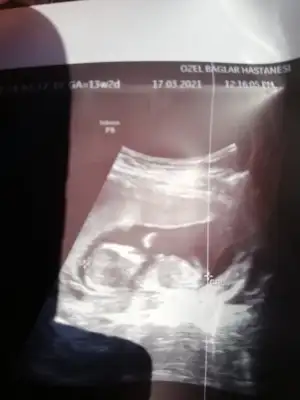

dr soylemeden siz gorun genital nub teorisi ( bebegin cinsiyeti)

Çok dik gelmedi cnm Dr erkek dedi demiştin ☺️

Canım 2 hafta önce doktor 11 haftalıkken erkek dedi 13 hafta başka doktora gittim oda bu hafta belli olmz ama aynı senn yöntemle paralel dedi kıza benziyor dedi yani nub yöntemini kullndı kime inannacagımı şaşırdım paraleldi gerçekten 13. Hafta da 11 dede dikti canım hangisi yanılıyor bilmiyorum